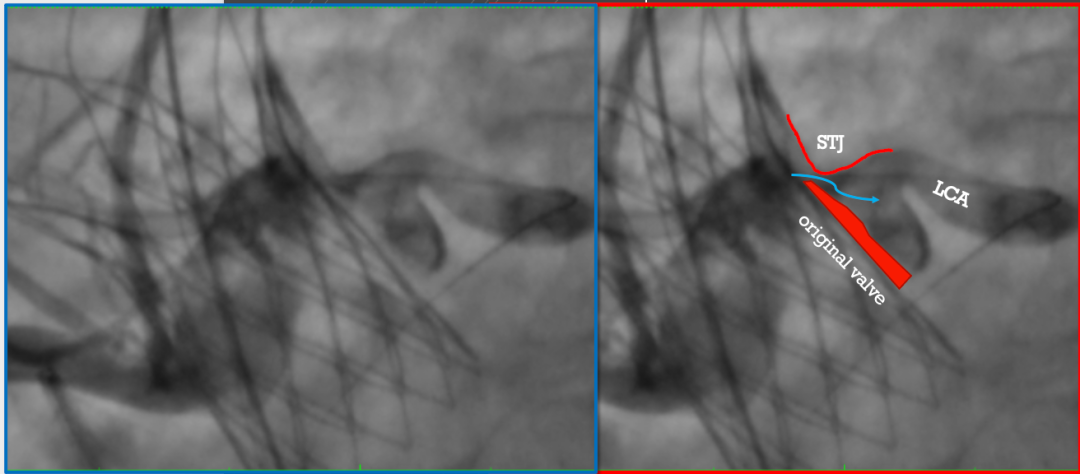

左冠风险评估

图片

右冠风险评估

• 术前CT预估21mm人工瓣膜植入后位置及STJ层面残余空间。患者右-无、双无冠状窦少量粘连,预计瓣膜植入后向左右冠窦方向偏移。

IVUS检查提示因原瓣叶遮挡,左冠开口受阻,最窄处残余缝隙0.66-0.82mm。

右冠开口残余1.56mm-3.46mm,血流无明显阻挡。